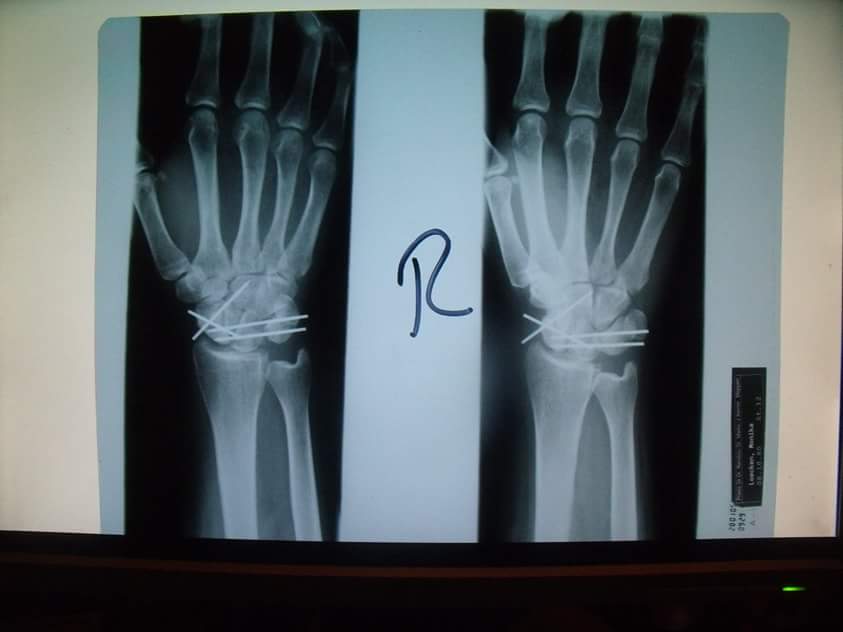

Röntgenbild nach der Teilversteifung/Fusion...:

Die Kirschnerdrähte wurden nach 6 Wochen ambulant entfernt. Danach gab es dann auch keine Gipsschiene mehr. Etwas, was ich dem Krankenhaus hoch anrechne ist: Am Abend der ambulanten Metallentfernung rief die Nachtschwester bei mir zu Hause an, um sich nach meinem Befinden zu erkundigen und wies auch nochmal daraufhin, dass - falls irgendetwas sein sollte - ich jederzeit dort anrufen oder vorbeikommen könne.

Es wurden regelmäßige Röntgenkontrollen gemacht, die bisweilen belegen, dass alles gut verheilt. Krankengymnastik bekam ich nach 6 Wochen und Ergotherapie kam später auch hinzu. Seit 5. Juni 2005 bin ich nun wieder "gesundgeschrieben". Leichte Schmerzen - vor allem nach Belastung - sind nach wie vor vorhanden. Die Bewegungseinschränkung ist im Vergleich zu vorher schon recht groß, aber das sind alles Sachen, an die ich mich gewöhnen kann und die mir tausend mal lieber sind, als ein komplett versteiftes Handgelenk.